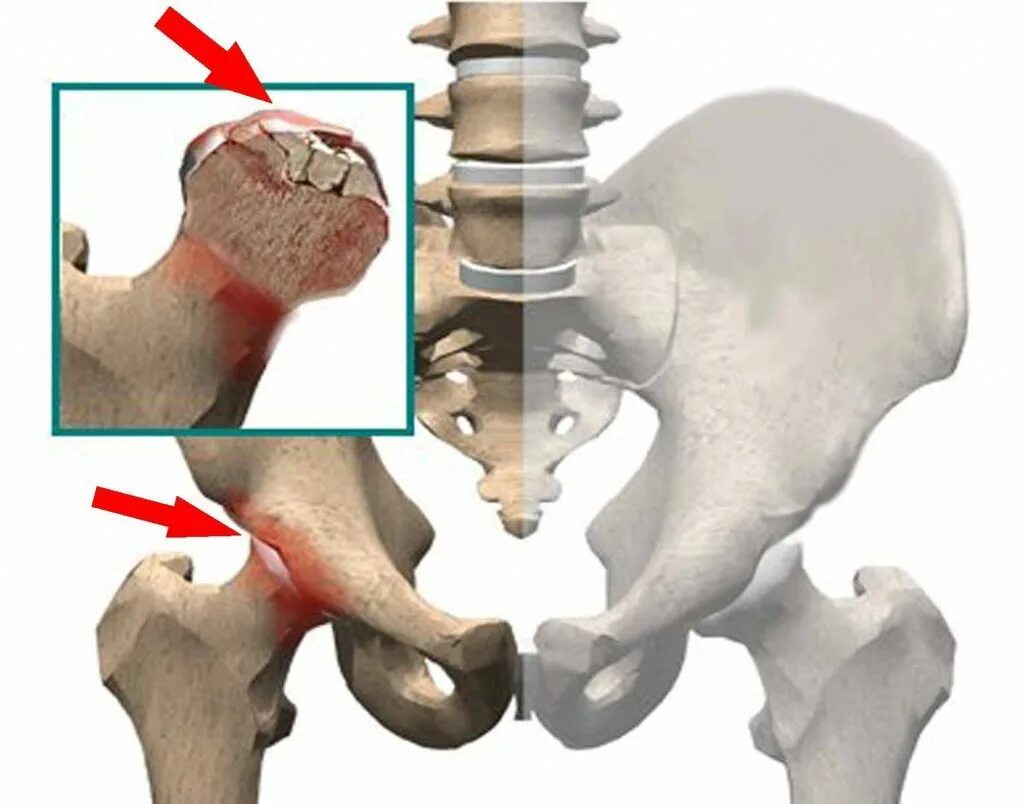

Перелом шейки бедра мкб 10 у взрослых